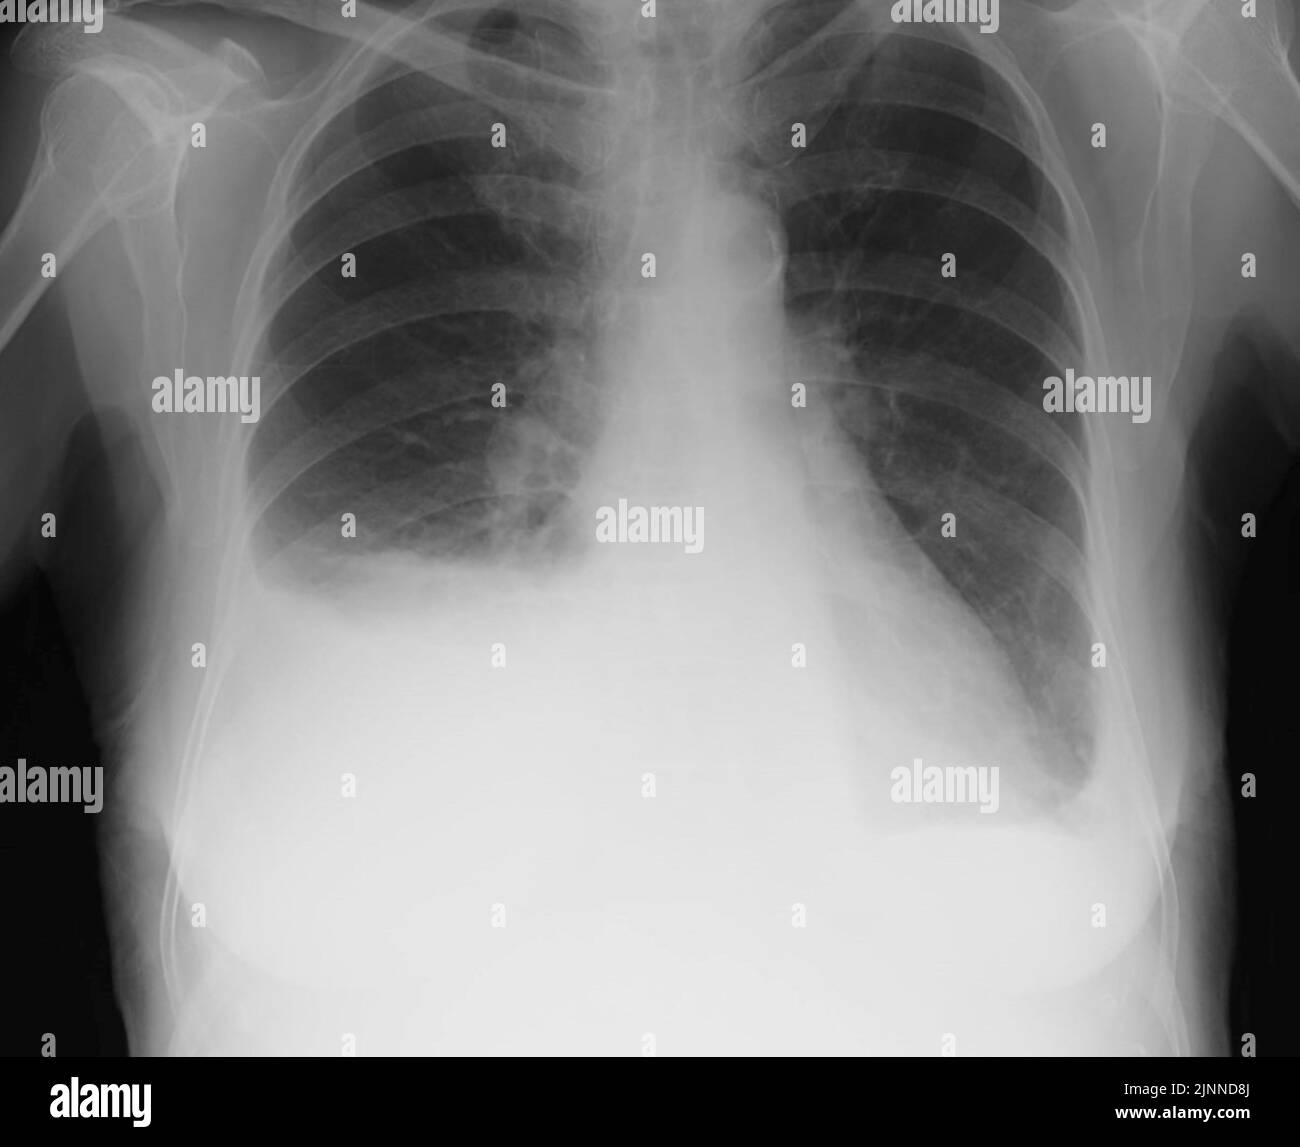

From www.alamy.com

Pleural effusion, Xray Stock Photo Alamy How To See Pleural Effusion On X Ray detection of pleural effusion (s) and the creation of an initial differential diagnosis are highly dependent upon imaging. pleural effusion, which some people call “water on the lungs,” is the buildup of excess fluid between the layers of the pleura outside your. Cxr, pocus, & review of prior radiology. different imaging modalities can be used to diagnose. How To See Pleural Effusion On X Ray.

Chest Xray showing B/L pleural effusion (L>R). Download Scientific How To See Pleural Effusion On X Ray different imaging modalities can be used to diagnose and manage pleural disease. Cxr, pocus, & review of prior radiology. pleural effusions can be entirely overlooked on supine radiographs or can be misdiagnosed as pulmonary consolidation or. pleural effusion, which some people call “water on the lungs,” is the buildup of excess fluid between the layers of the. How To See Pleural Effusion On X Ray.